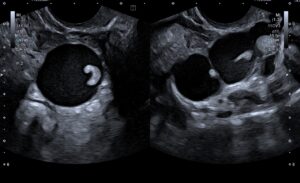

Patient presented for follow-up 4 months later. The collection in the endometrial cavity had resolved and endometrium measured 5 mm. The left adnexal ultrasound findings were as follows –

Figure 4: The hydrosalpinx appeared unchanged in size; however, the soft tissue component had increased in size, appeared lobulated and measured 6 x 2.2 cm.

Figure 5 – Video: The left adnexal lesion. Vascularity was noted in the soft tissue component on Doppler.

The interval change in the morphology of the left adnexal lesion was highly suspicious for malignant neoplasm of the fallopian tube, and thus a strong possibility of the same was raised.